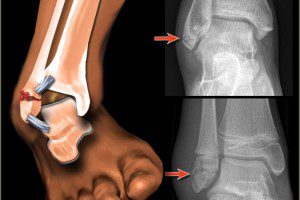

Трещина кости в области лодыжки

Основная причина травм лодыжки – высокая нагрузка на нижние конечности. Типична для людей, занимающихся спортом, балетом и цирковой акробатикой. Однако зачастую перегрузки сопровождают и садоводов, которые стремятся получить как можно более высокий урожай.

В то же время трещина в лодыжке может образоваться по банальной неосторожности. Достаточно оступиться на ступеньке или на неровном тротуаре, особенно когда женщина идёт на высоких каблуках.